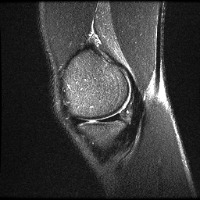

meniscal Computer Vision Project

Medical Diagnostics: Radiologists, orthopedic surgeons, and other medical professionals can utilize the "meniscal" model to accurately identify and classify meniscal lesions in knee MRI scans, thus improving the diagnosis and treatment process for patients with knee-related injuries and conditions.

Sports Injury Prevention and Management: Sports rehabilitation centers and athletic trainers can employ the "meniscal" model for analyzing knee scans of athletes to assess the health of their knees, track any changes over time, and tailor training regimens or treatments to prevent or recover from meniscal injuries.

Pre- and Post-Surgery Evaluation: Surgeons can use the "meniscal" model to analyze the knee scans taken before and after meniscal surgeries to evaluate the efficacy of the surgical intervention and make informed decisions about the patient's further treatment plan and rehabilitation process.